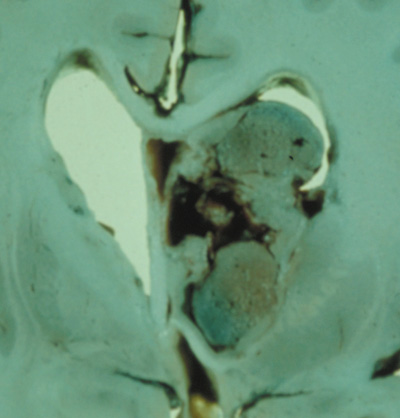

Optic nerve gliomas may involve the optic chiasm and be associated with endocrine disorders or nystagmus.68–70 Surgical excision of chiasmal gliomas (Fig. 6) carries a high risk of visual loss. Invasion of the hypothalamus or the third ventricle carries a poor prognosis, with greater than 50% 15-year mortality rate.71 One review of radiation treatment for chiasmal gliomas collated data from small case series and found no significant long-term improvement in visual function, progression, or mortality with radiation treatment.71 Other reports suggest that radiation doses over 4500cGy improve symptoms and slow progression of chiasmal gliomas over several years.72 Adequate tumor coverage by radiotherapy results in irradiation of normal brain and nearly all children need hormone replacement.73 Chemotherapy is an alternative.74,75

|